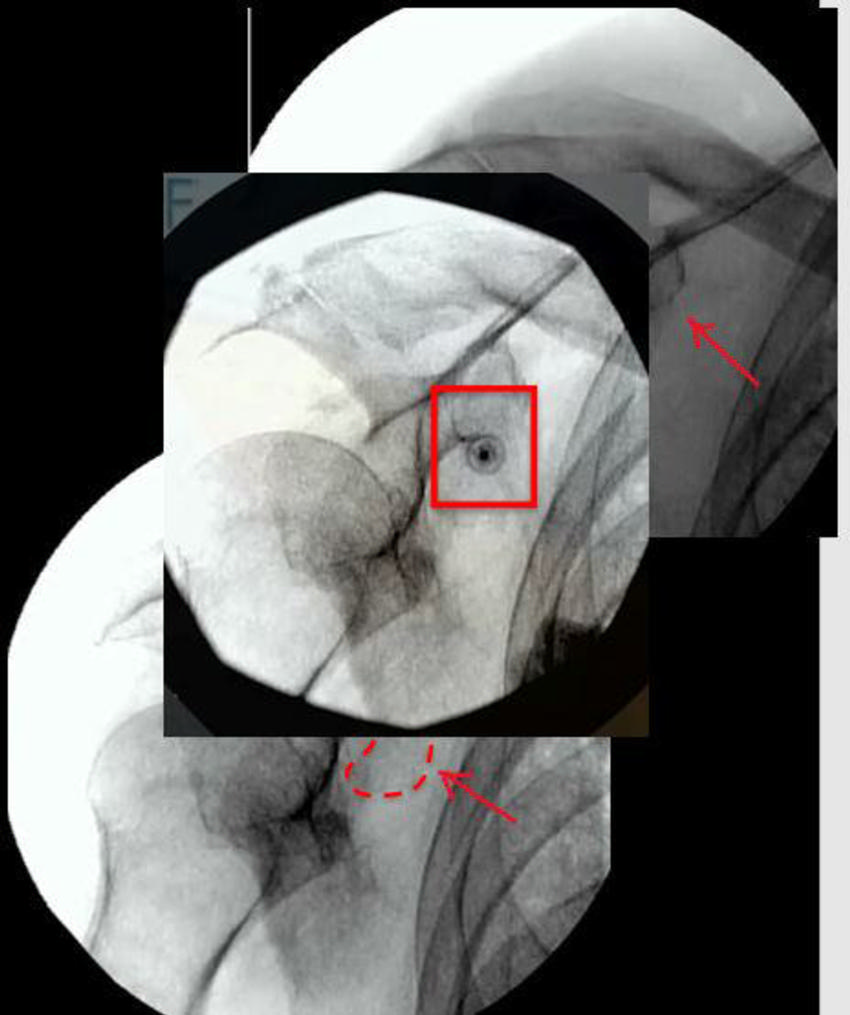

Figure 12. Hip-specific cooled radiofrequency ablation technique: There are three ablation targets.

Figure 13. Hip cooled radiofrequency ablation: Obturator nerve ablation.